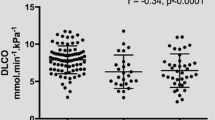

In the total collective, there is a mean VC of 3.78 L. On average, the VC shows a slight undercut of the respective predicted value (mean 92% pred.), while the results of the CLT are in line with the norm (mean 105% pred.). On average, sRt is elevated (mean 1.35 kPa s). In addition to a reduced FEV1 (mean 84% pred.), an increased residual volume is also notable (mean 133% pred.). Subjects in the subgroups obstructive ventilatory disorder (sub-2) and lung function or HR-TCT findings indicating emphysema (sub-3) have correspondingly elevated RV/TLC values (mean 135% pred. and 127% pred., resp.). In subjects without further pulmonary or cardiac diseases, there are no relevant deviations from the respective predicted values, whereas the results of patients with cardiac diseases correspond to the average values of the total collective (see Table 2). CO diffusion capacity (DLCO) shows decreased values in the total study population (mean 70% pred.), and patients without further pulmonary or cardiac diseases also have lower results compared to the respective predicted values (mean 86% pred.). Individuals from the subgroup lung function or HR-TCT findings indicating emphysema (sub-3) have the worst diffusion capacity (mean 59% pred.). Figure 1 presents the box plots of the measured DLCO values for the subgroups.

Diffusion capacity DLCO proves to be the most indicative measurement parameter with a correlation to fibrosis of ρ = − 0.315 (P < 0.01) (Fig. 2a) and a nearly seven percent difference in DLCO between patients with and without fibrosis (mean 68.1% pred. and mean 75% pred., resp.). In subgroup analysis, especially in subjects with concomitant cardiac diseases (sub-1) and in subjects with obstructive ventilatory disorder (sub-2), meaningful correlations stand out (each ρ = − 0.297, n.s.). Evaluation of the fourfold tables shows that diffusion measurement detects fibrotic remodeling processes with a sensitivity of 73%. Fifteen subjects with fibrosis have a VC ≥ LLN. Forty of 45 patients with DLCO < LLN have pulmonary fibrosis (PPV 89%). With a resulting 71% accuracy, DLCO has good informative value for the diagnosis of fibrosis. According to Landis and Koch, the relationship between these parameters is "fair" with a Cohen’s κ of 0.29 [33]. High agreement with DLCO is also found in the fourfold tables in patients with obstructive ventilatory disorder and in patients with lung function pattern indicating emphysema (accuracy 78%, 88%, resp.; κ = 0.31, 0.59, resp.).

a Comparison of vital capacity and diffusion capacity with pulmonary fibrosis (point value of Score A). VC: n = 72, ρ = -0.168, n.s.; DLCO: n = 69, ρ = -0.315, P < 0.01. b Comparison of vital capacity and diffusion capacity with pleural plaques (point value of Score B). VC: n = 72. ρ = -0.273, P < 0.05; DLCO: n = 69. ρ = -0.175, n.s

In the overall cohort, DLCO shows only a weak correlation with pleural plaque expression (ρ = − 0.175, n.s.) (Table 5). In the patient group with no other pulmonary or cardiac diseases (sub-4), the negative association becomes more evident (ρ = − 0.25, n.s.). In the fourfold table of the total study group, however, DLCO shows a higher meaning for the presence of pleural plaques with 61% accuracy than VC (39% accuracy). The PPV for the presence of pleural plaques in reduced CO diffusion capacity is 82%. Nineteen patients with pleural plaques have a DLCO ≥ LLN.

The correlations between lung function parameters and fibrosis and pleural plaque scores (Scores A and B) in our study show that VC is a good predictive parameter regarding the expression of pleural plaques (ρ = − 0.273, P < 0.05). DLCO shows a strong relation to the extent of asbestos-related fibrosis (ρ = − 0.315, P < 0.01), confirming the results of Barnikel et al. [35]. Likewise, Manners et al. (2017) showed a strong correlation between DLCO and radiologically visible expression of interstitial pulmonary fibrosis in an asbestos-exposed collective [36]. In the fourfold table, however, DLCO shows higher accuracy and sensitivity regarding the presence of pleural plaques in our study compared to VC (accuracy 61%, 39%, resp.; sensitivity 66%, 26%, resp.). These results thus confirm the essential role of DLCO measurement in the early detection of asbestos-related alterations in the lungs in addition to the established method of VC measurement [37]. Therefore, both measurement methods should be used in the context of control and preventive examinations of persons formerly exposed to asbestos. The supplementary measurement of DLCO/VA is useful at most in asbestos-exposed patients without further pulmonary or cardiac diseases but generally does not allow relevant conclusions to be drawn about morphological alterations in the lungs. This confirms the results of van der Lee et al. (2006); these authors also did not see any additional diagnostic benefit of the transfer coefficient in the detection of pulmonary disease and, in particular, interstitial lung disease [38].

Another aim of the study was to assess the influence of pulmonary emphysema and other possible confounding factors on the relationship between changes in lung function (especially diffusing capacity) and previous asbestos exposure. Emphysema can cause an attenuation of the DLCO [24]. When analysing individuals exposed to asbestos who also have emphysema, it is difficult to distinguish whether the reduced DLCO value is caused by the asbestos-induced remodeling processes in the lung or by the emphysema. Therefore, the subgroup of subjects with emphysema was evaluated separately. This approach was confirmed by the results of the subgroup analysis, which show that DLCO is worst in patients with emphysema (sub-3) (see Table 2). The study presented here also demonstrates a substantial worsening of DLCO values in patients with concomitant cardiac diseases (sub-1). It can thus be assumed that reduced cardiac performance has a negative impact on DLCO as well [40]. However, the groups sub-2 and sub-4 also included several patients with reduced DLCO. Therefore, it is postulated that in all subgroups, asbestos-related changes contribute to the limitations of DLCO, which is reflected in the negative correlation of DLCO with Score C in the overall collective. A previous study, which excluded patients with concomitant diseases such as emphysema or heart failure, detected a significant reduction in DLCO associated with inhalation of asbestos fibre dust [10].